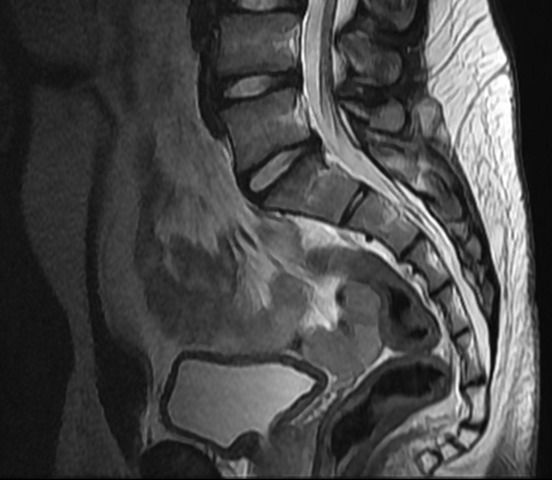

• Imagen por resonancia magnética

Imagen por resonancia magnética

Otras técnicas no invasivas que se han desarrollado incluyen el uso de ultrasonidos para obtener imágenes de los tejidos blandos y la aplicación de la resonancia magnética nuclear con fines diagnósticos y de investigación.